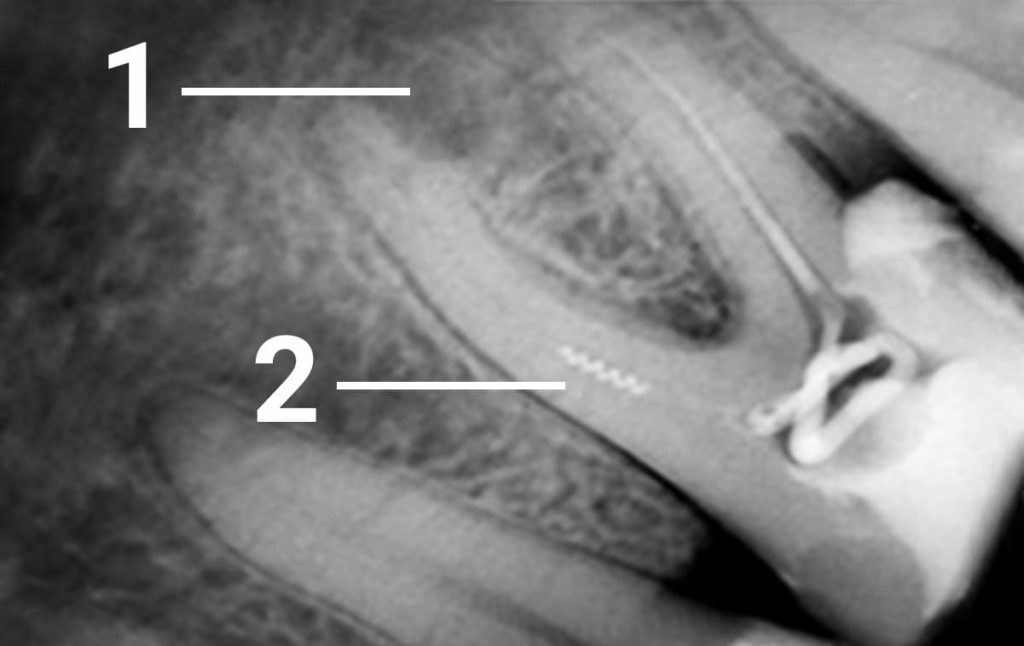

1. Patient of another clinic where he underwent endodontic treatment of tooth 36 came with pain complaint in this tooth. The reason a broken endodontic instrument (root canal filler) got stuck in the medial canal which hampered properly filling the root canal. Some years later, it led to periodontitis. 1- destruction of the bone tissue due to an incomplete treatment of the root canal 2 - spiral fragment of an intratubular tool